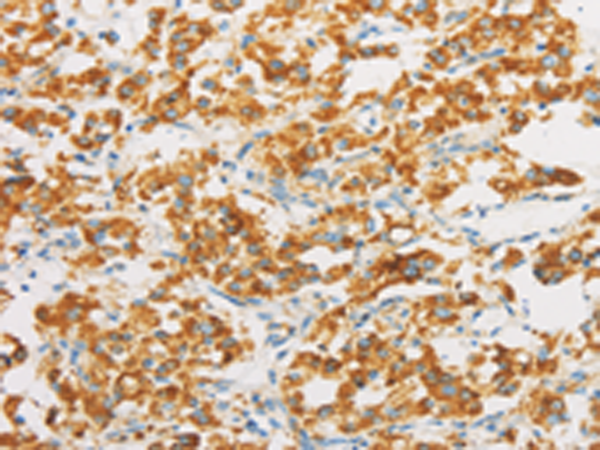

IHC positive control: |

Human thyroid cancer and human cervical cancer |

IHC Recommend dilution: |

25-100 |